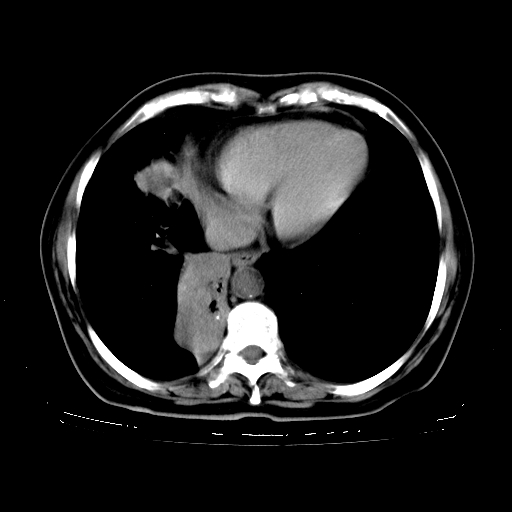

女,70岁,咳嗽、咳痰一个月,低热一周。

2.胸主动脉夹层。

4、主动脉夹层。

支持,首先一元论解释。胸主动脉部分层面环形低密度,中心强化。环形影不强化。不象真假腔的改变。我考虑动脉炎,不太支持夹层动脉瘤-和大家的观点不一致,希望楼主让患者再做个心血管的彩超吧。

继发型肺结核,右下肺支气管内膜结核.右侧少量胸腔积液.主动脉夹层.